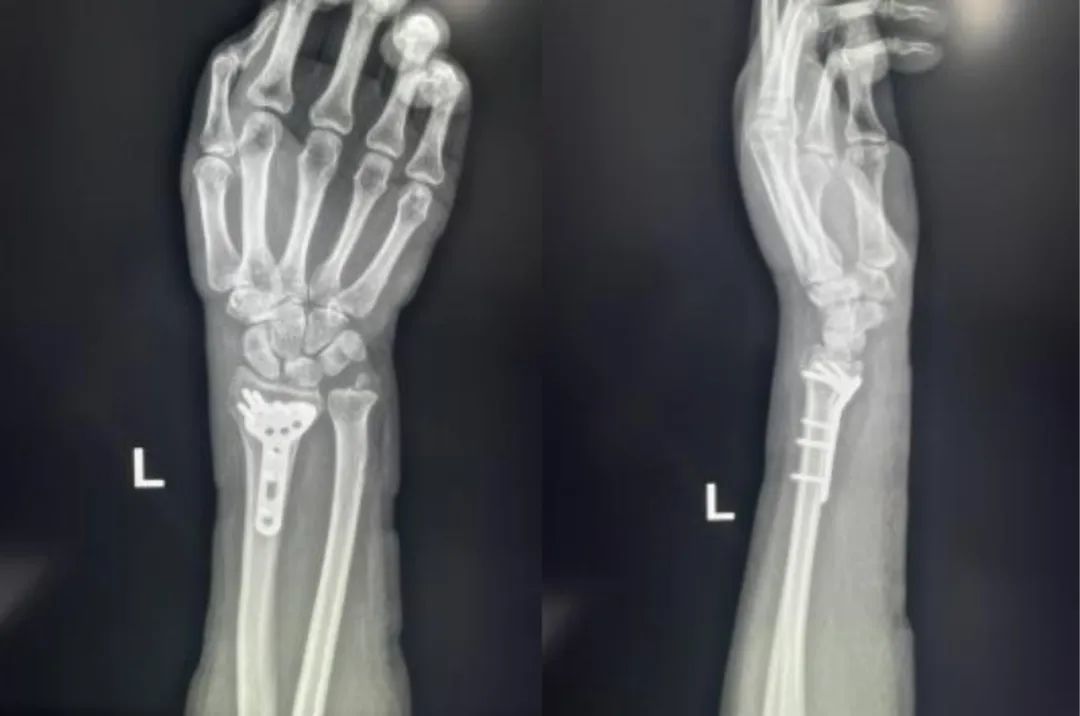

次に、手と手首のX 線検査を依頼される可能性があります。画像では、三角筋骨折は、小さな骨片が三角筋の後ろから剥がれたように見えます。

ただし、三角骨骨折は、X 線でも見えにくいことがあります。 X 線検査で何も写らない場合、医師はCT スキャンを指示することがあります。これは、手と手首の骨と筋肉の断面図を示しています。

• 重度に折れた骨を通常はピンまたはネジで修復する